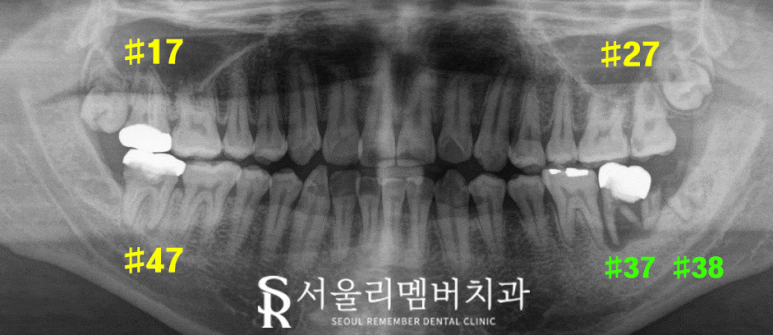

검진 및 진단

시작하기에 앞서 정확한 진단을 위한

파노라마 X-ray를 살펴보았습니다.

17번, 27번, 47번 치아는 우식 및 염증이 있어

근관 제거가 필요하고,

37번과 38번 치아는 부러져 발치가

필요한 상태라는 것을 확인했습니다.